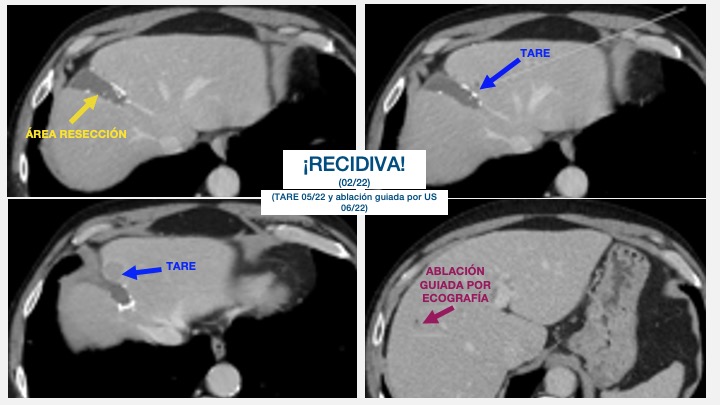

- Ablacion estereoataxia lesiones hepaticas 04